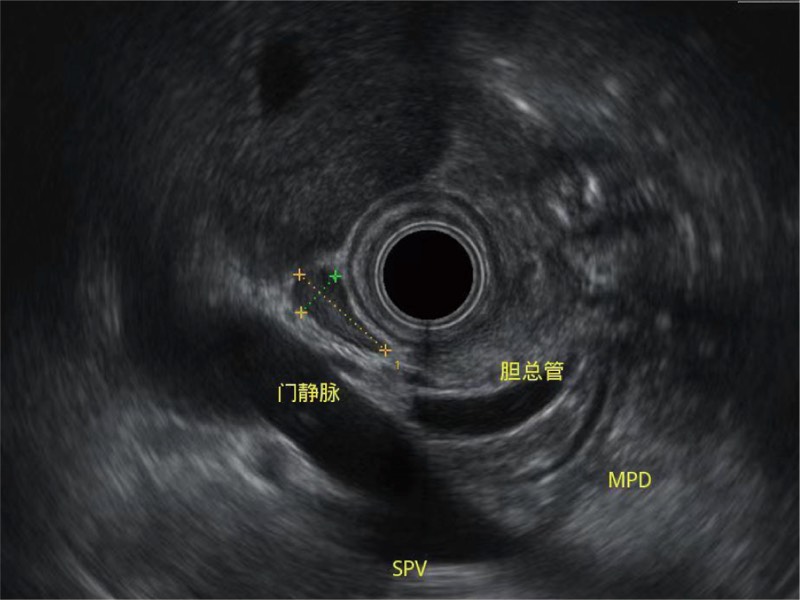

• 清晰显示胆总管及周围血管分布